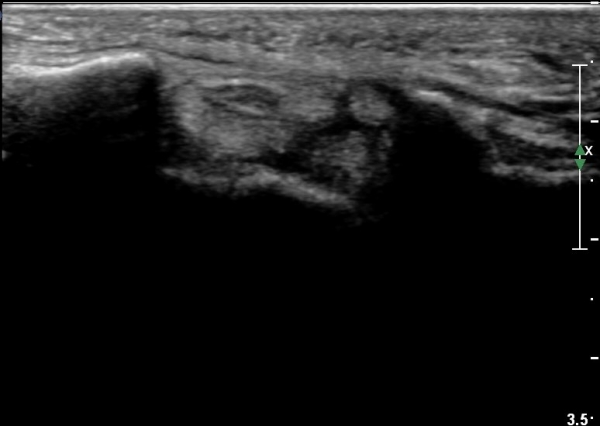

¼Õ¸ñÀÇ È¾´Ü¸é°Ë»ç¿¡¼­ Á¤Á߽ŰæÀÇ ºÎÁ¾ µî ƯÀÌ ¼Ò°ßÀÌ º¸ÀÌÁö ¾Ê´Â´Ù(»çÁø 1).